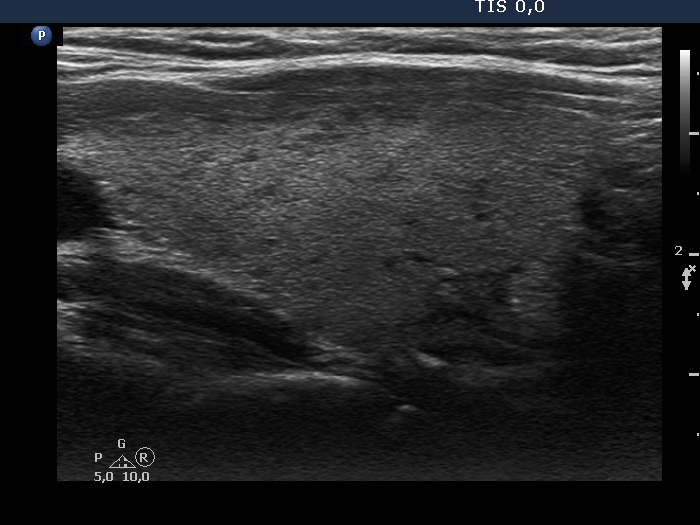

Right lobe, longitudinal scan

Left lobe, longitudinal view. The echogenicity index is around 5%.